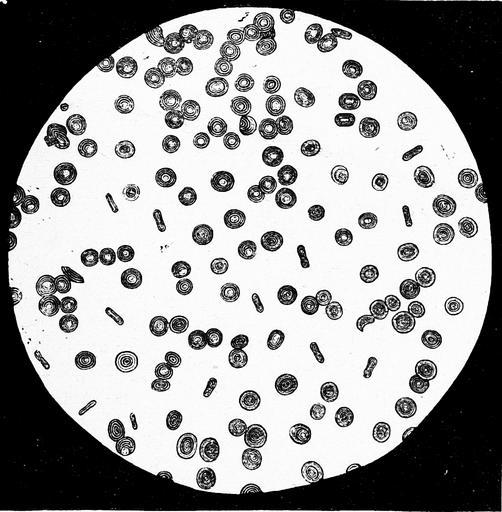

MAKE A MEME View Large Image Die Gartenlaube (1876) b 697 2.jpg 697 698 Images from Gartenlaube requiring categorisation